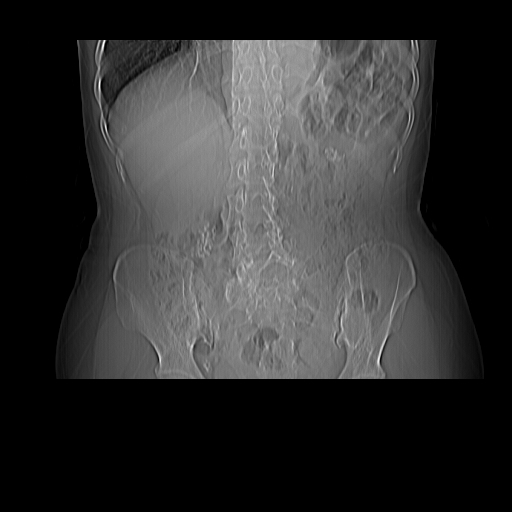

女45y多次(7次)碎石,结果不理想!曾碎石后尿出小碎石,仍腰痛,要求ct,其它不详.本人更倾向于钙化斑!无肾实质破坏,积水等提示集合系统无梗阻.另外腹腔多处钙化.是否结核后改变!谢谢赐教!

1)双肾结石。2)脾脏钙化灶。3)腹膜后多发淋巴结钙化。

尿路结石与腹部淋巴结钙化共存,建议v尿路造影检查,免得钙化灶冤枉为结石受罚。

考虑双肾结石,肾脏实质无破坏表现,没有结核病史,不考虑肾结核,